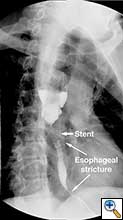

A 49 year old male presented to our institution with significant dysphagia and a 40 lb. weight loss secondary to a distal esophageal stricture. The patient had ingested lye 4 years previously and required partial gastrectomy, gastrojejunostomy, and partial colectomy at an outside institution at that time. His symptoms of dysphagia had progressively worsened despite repeated dilations and placement of an esophageal stent (Figure 1). Surgical reconstruction was therefore felt to be indicated. Preoperative computerized tomography angiogram did not clearly display the blood supply to the stomach, but did show that the colonic vasculature was adequate for use as a conduit if needed.